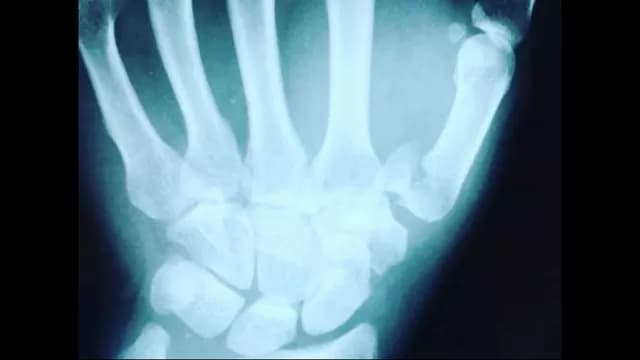

Cuando se encontraba recorriendo la vuelta 11 de la competencia de la categoría 250 cc en La Chutana de Santa Rosa, Aída Martínez sufrió una aparatosa caída y sufrió la fractura de su muñeca izquierda.

Dentro de las fotografías que publicó en la mencionada red social, Aída Martínez mostró cómo le quedó la muñeca. Se puede ver la mano izquierda hinchada, así como la radiografía de su lesión. La modelo tendrá que ser operada.